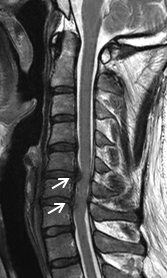

術前MRIでは多椎間で脊髄(灰色)を圧迫しています。後方手術施行後、脊髄への圧迫は改善しています。